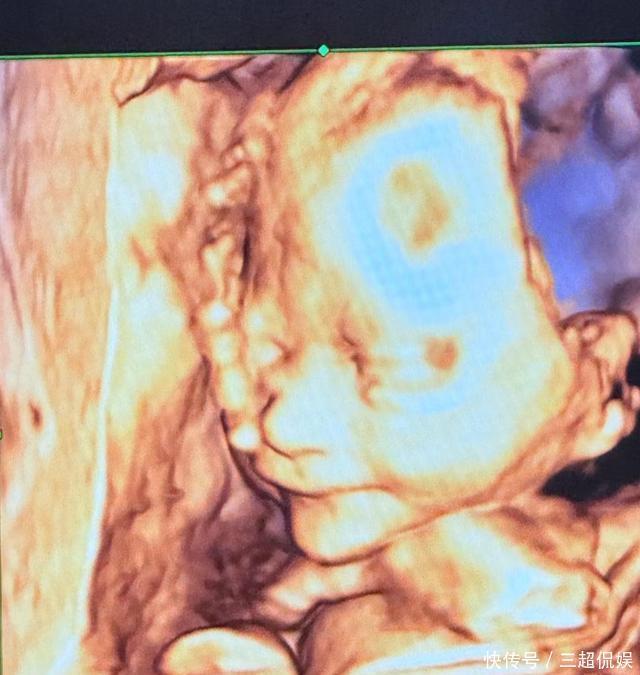

两东谈主成婚也算是娱圈比拟扯旗放炮的事情了,如今十年当年了,两东谈主又迎来了二胎面便条,包文婧孕珠之后也莫得罢手使命,每天会纪录我方的生涯,还需要关心大男儿的学习,也算长短常穷困了,包贝尔有了二胎之后亦然劲头王人备。

在孕早期包文婧还有点情谊崩溃,但现时孕晚期加上有一胎的告戒,通盘东谈主也很是千里稳,这在下给面便条准备好了扫数降生用品,回来包文婧就准备要进组拍戏了,何况表露导演是包浑厚,没念念到包贝尔还有一刻导演的心。

在3月19日,包文婧晒出我方打理行囊的视频,少量不矫强,坐在地上就打理起来了,孕珠8个月依然是孕晚期按酷好酷好需要多多休息,但包文婧我方也停不下来,加上又是给老公助力,当然是要去的。

包文婧孕8月还忙进组拍戏!表露导演是老公,亲身打理行囊不矫强,孕珠的包文婧穿戴紧身毛线连衣裙少量没胖,皮肤白,带上我方常用的东西就开拔成都了澳门永利真人百家乐,期待她的新作品。